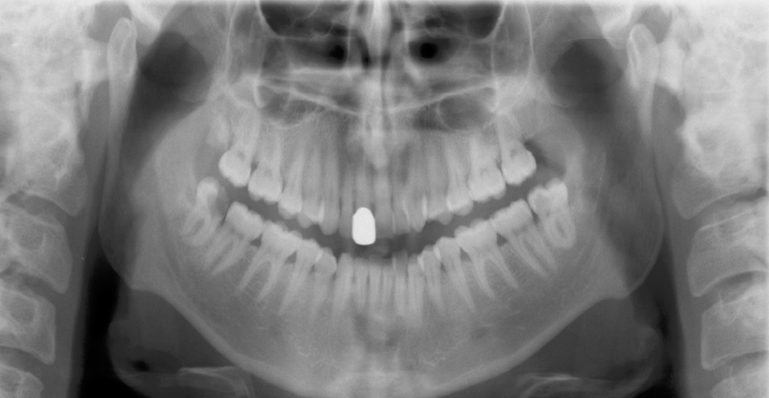

What is wrong with this image?

too far forward

double real image of cervical spine (superimposed on ramus)